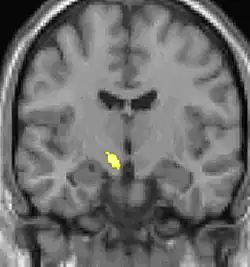

Neuro-imagerie

La morphométrie voxel par voxel (VBM) montre les différences structurelles des zones du cerveau

Les images par tomographie à émission de positron indiquent les régions du cerveau qui sont activées lors de la douleur, par rapport aux périodes sans douleur. Elles montrent les régions du cerveau qui sont toujours actives durant la douleur en jaune/orange (appelé "matrice-douleur"). La zone au centre (dans les trois vues) est spécifiquement activée uniquement pendant la crise. Les photos sur la ligne du bas (effectuées par VBM) montrent les différences structurelles entre les patients souffrant d'AVF et des personnes saines : seulement une partie de l'hypothalamus est différente[50],[51].

Il semble exister des anomalies microstructurales hypothalamiques bilatérales (en l'occurrence l'existence d'une hypertrophie)[52] sans que l'on sache si ces anomalies sont la cause ou la conséquence de la répétition des crises.